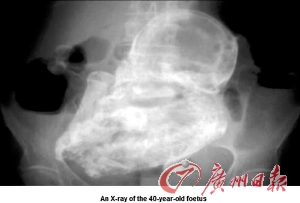

82歲老婦腹腔石胎 40年未察覺

【byb.cn 】(來源:)廣州日報 本報訊 據外媒報道,哥倫比亞首都波哥大一名82歲老婦,8日因腹痛就醫(yī),醫(yī)師驚訝地發(fā)現,造成她腹痛的原因,竟是一個已形成40年的“石胎”(如圖)。

起初醫(yī)師以為老婦是因為寄生蟲或是膽結石導致腹痛,但察覺老婦腹部有異狀,經X光檢驗才查出老婦體內居然有一個胎兒,而且胎兒在老婦體內長達40年,由于胚胎未在子宮里發(fā)育,移到患者的腹腔,導致胚胎無法正常生長,鈣化后形成“石胎”。

德州內分泌與生殖專家伯格博士表示,子宮外孕(異位妊娠)通常的位置常在輸卵管,少數案例發(fā)生在腸、卵巢,甚至在主動脈,這些罕見的位置對病患而言非常危險。這名老婦目前已轉院,將接受手術移除“石胎”。